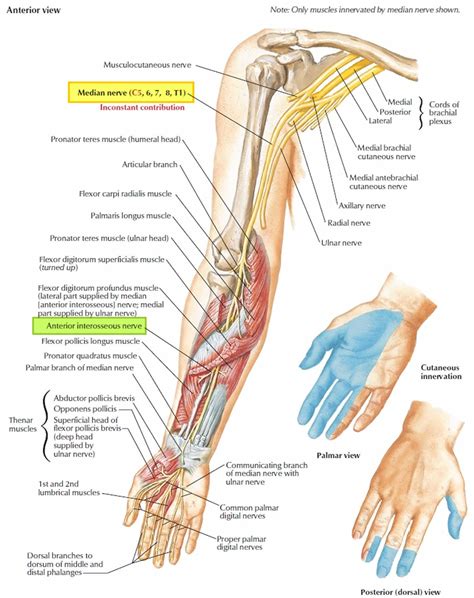

The Posterior Interosseous Nerve (PIN) begins its journey as the deep branch of the radial nerve. It travels through the forearm, passing beneath a critical anatomical structure known as the Arcade of Frohse—a fibrous arch at the origin of the supinator muscle. Once it passes this site, it provides motor innervation to the following muscles:

• Extensor Digitorum: Allows for the extension of the fingers.

• Extensor Carpi Ulnaris: Facilitates wrist extension and ulnar deviation.

• Extensor Digiti Minimi: Controls the extension of the little finger.

• Abductor Pollicis Longus: Assists in thumb abduction.

• Extensor Pollicis Brevis: Controls thumb extension.

• Extensor Pollicis Longus: Vital for extending the distal phalanx of the thumb.

• Extensor Indicis: Specifically controls the extension of the index finger.

Because the PIN is almost exclusively a motor nerve, it does not provide sensory information to the skin. This is a crucial diagnostic differentiator; if you are experiencing significant pain or numbness in the skin of the forearm or hand, the source of the issue may be a more proximal injury to the main radial nerve rather than an isolated compression of the Posterior Interosseous Nerve.